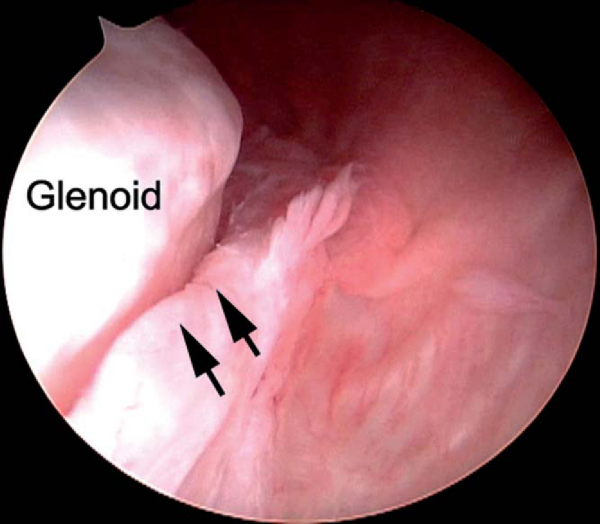

A systematic diagnostic arthroscopy is performed. The superior and posterior labral attachments are inspected. If they are torn, arthroscopic repair is performed as described in

before anterior pathologic processes are addressed. With anterior instability, the anteroinferior labral attachment is often disrupted (Bankart lesion). Chronic instability often results in a medialized capsulolabral complex (anterior labral periosteal sleeve avulsion [ALPSA lesion];

Fig. 3-6

). When it is present, this labral attachment must be sharply reflected from the glenoid and then reattached to the articular margin. The anteroinferior glenoid is evaluated for bone and cartilage loss and the posterosuperior humeral head for a bony or cartilaginous Hill-Sachs defect (

Fig. 3-7

).

Figure 3-6 |

Figure 3-7 |